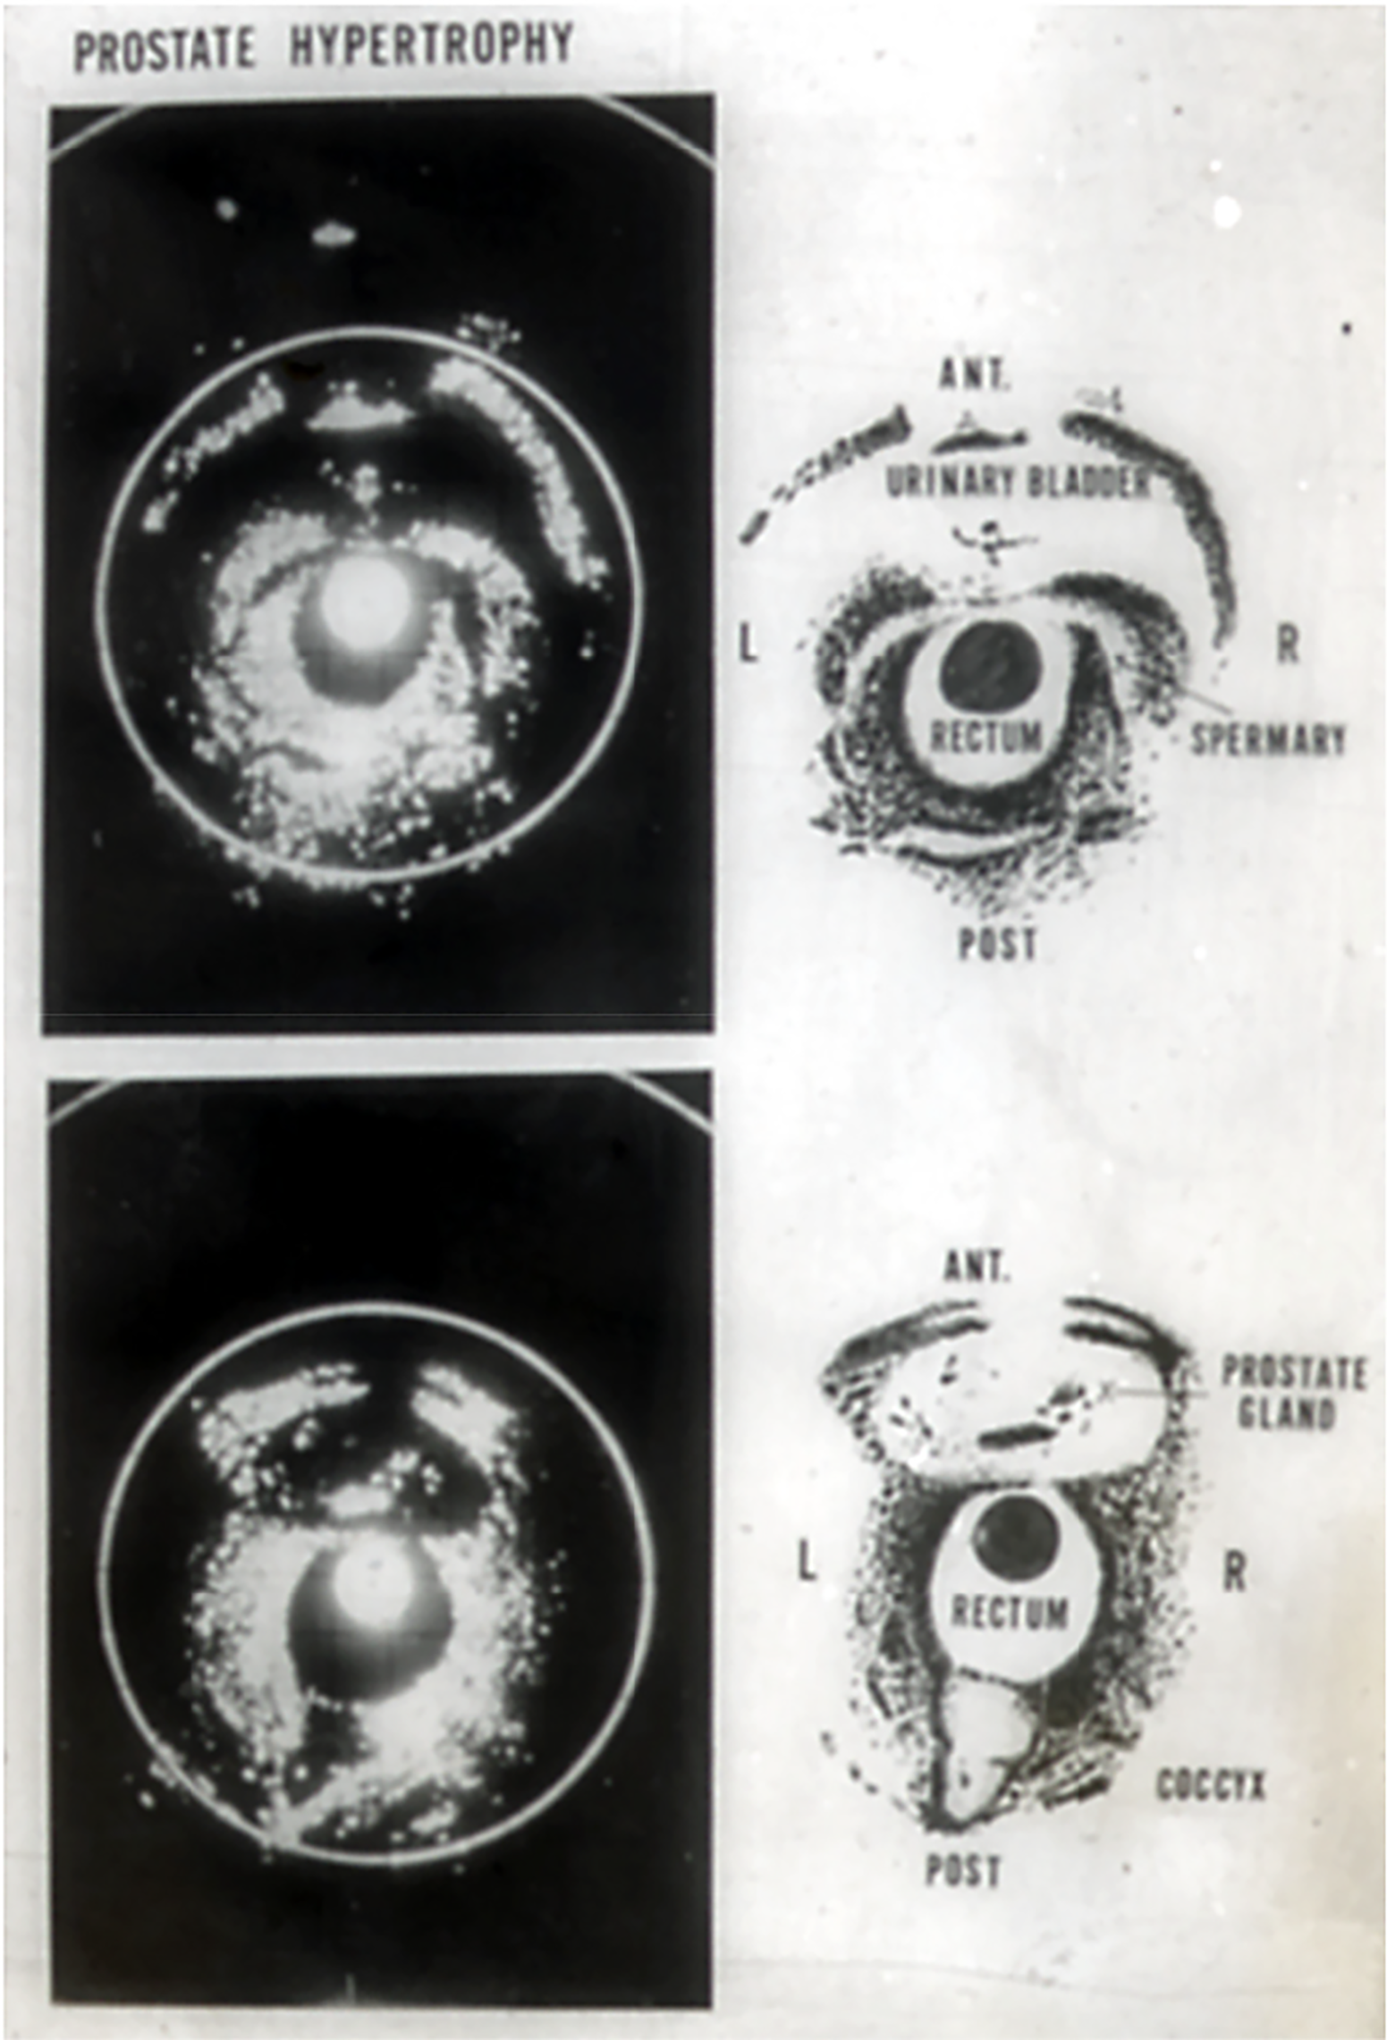

The next day, I persuaded one of my patients to undergo a new type of examination and brought him to Dr. Tanaka’s laboratory. The patient was positioned on the examination bed for cystoscopy, and the probe was carefully inserted into the rectum. The images we obtained at that time are shown in Figure 1. In the upper image, the urinary bladder with an inserted balloon and the seminal vesicles behind it are visible, while in the lower image, the prostate with some calculi inside is clearly shown. Without a doubt, this was the first time the prostate had been imaged in a living human body, occurring more than 10 years before the advent of CT. I was deeply impressed by this achievement, considering the potential for future advancements in the technique, which promised to greatly enhance both diagnosis and treatment of prostate diseases.

Figure 1: World’s first practical transrectal ultrasonotomogram of the urinary bladder with the seminal vesicles (upper) and the prostate (below) (Watanabe-Tanaka, 1967)